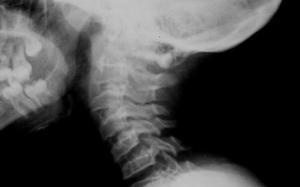

Boyun bölgesinde 7 adet vertebra vardır bu vertebralar yandan tepe noktası boynun ön bölgesi olan ’C ‘ harfini andırır. Boyun bölgesindeki omurga eğriliğini servikal lordoz olarak ifade ediyoruz. Bu eğri tamamen normaldir ve aslında arzu ederiz, çünkü kafa ve omurganın stabilize edilmesine yardımcı olur. Fakat eğrinin düzleşmesi yani fizyolojik lordoz olarak ifade ettiğimiz açının azalması yada kaybolup ’ I ‘ şeklini alması durumunda boyun düzleşmesi olarak ifade ettiğimiz klinik tablo ile karşı karşıya kalırız. Hatta bu eğri daha da ilerleyip tersine açılanma gösterirse tablonun daha ciddi bir hal alması söz konusudur.

Düz bir servikal omurga, şok absorbe etme kabiliyetini kaybeder. Bu da disk üzerinde ekstra bir baskı oluşturur ve diskin daha kolay bir şekilde kırılmasına neden olur ki bu durum ilerleyen süreçte vertebra dejenerasyonuna neden olur. Bu sorun tıp dilinde dejeneratif eklem hastalığı , dejeneratif disk hastalığı veya osteoartrit olarak adlandırılır.

Servikal omurganın düzleşmesi ve ilerleyip ters ‘C’biçimini alması durumunda boynun arka tarafındaki tüm anatomik yapılar gerilir. Vertebral atardamarlar da da gerilim söz konusu olacağından çaplarında daralma ve beyne giden kan akımında azalma söz konusudur. Bu, baş dönmesi, baş ağrısı, mide bulantısı, yorgunluk, kulak çınlaması, ağrı, sinirlilik, uykusuzluk, yüksek tansiyon ve kafa karışıklığına neden olabilir.